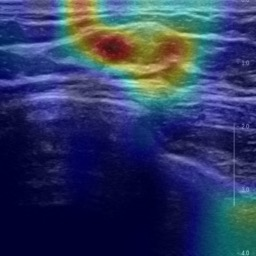

Ultrasonography is an important routine examination for breast cancer diagnosis, due to its non-invasive, radiation-free and low-cost properties. However, it is still not the first-line screening test for breast cancer due to its inherent limitations. It would be a tremendous success if we can precisely diagnose breast cancer by breast ultrasound images (BUS). Many learning-based computer-aided diagnostic methods have been proposed to achieve breast cancer diagnosis/lesion classification. However, most of them require a pre-define ROI and then classify the lesion inside the ROI. Conventional classification backbones, such as VGG16 and ResNet50, can achieve promising classification results with no ROI requirement. But these models lack interpretability, thus restricting their use in clinical practice. In this study, we propose a novel ROI-free model for breast cancer diagnosis in ultrasound images with interpretable feature representations. We leverage the anatomical prior knowledge that malignant and benign tumors have different spatial relationships between different tissue layers, and propose a HoVer-Transformer to formulate this prior knowledge. The proposed HoVer-Trans block extracts the inter- and intra-layer spatial information horizontally and vertically. We conduct and release an open dataset GDPH&GYFYY for breast cancer diagnosis in BUS. The proposed model is evaluated in three datasets by comparing with four CNN-based models and two vision transformer models via a five-fold cross validation. It achieves state-of-the-art classification performance with the best model interpretability.